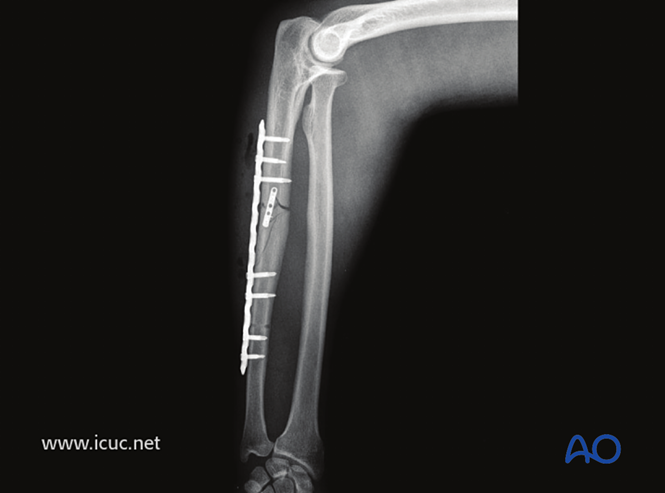

使用很长的锁定加压钢板(LCP)为这一复杂的尺骨中段骨折提供足够的固定。

正位片显示肱桡关节复位良好。

采用桥接固定联合复位钢板治疗该复杂孟氏骨折。

遗憾的是,骨折部位存在轻微间隙。如果在固定完成后移除小钢板,愈合可能会更快(见下文)。

4周时骨折仍可见,但肘关节复位良好。

X线检查●应按照当地诊疗规范进行随访X线检查。建议在2周时进行X线检查,确保桡骨头位置保持良好,之后在6周、12周和1年时检查,评估尺骨愈合情况。●若X线显示尺骨愈合进展满意,约术后8周可开始负重。●该病例展示了孟氏骨折术前和术后的X线影像。

术后